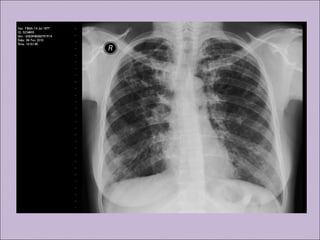

Manifestações sino-pulmonaresManifestações sino-pulmonares

C) Anormalidades persistentes à radiografia de tórax

Manifestações sino-pulmonaresManifestações sino-pulmonares A)Colonização / infecção persistentes por patógenos típicos da FC como Staphylococcus aureus, Haemophilus influenzae, Pseudomonas aeruginosa e Burkholderia cepacia B) Tosse crônica e produtiva C) Anormalidades persistentes à radiografia de tórax D) Obstrução das vias aéreas E) Pólipos nasais, sinusite F) Baqueteamento digital Rosenstein. J Pediatr. 1998;132:389-95